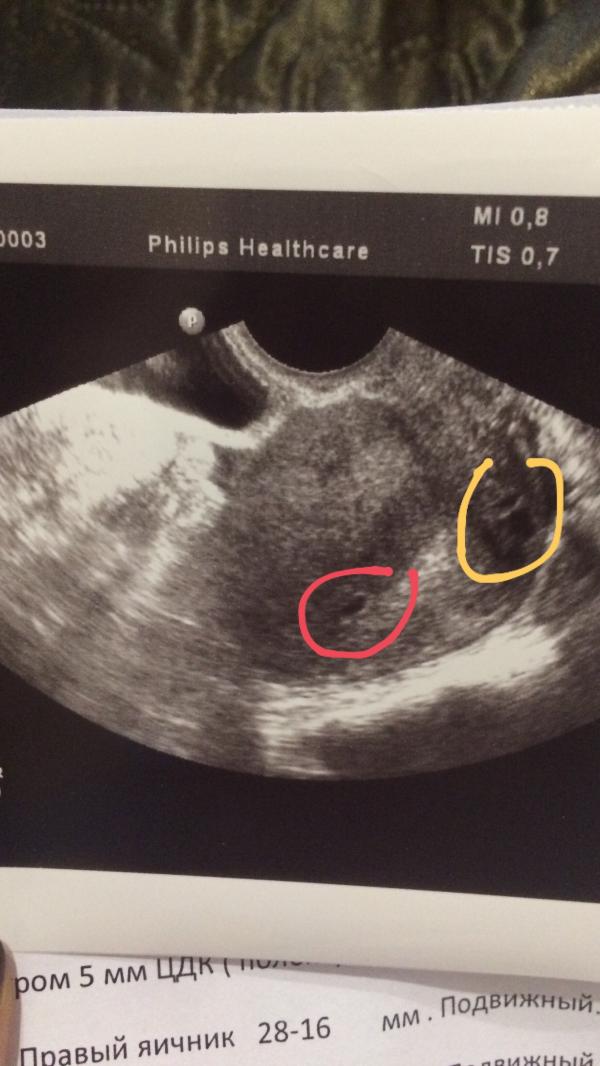

Врач заверил что плод один

Но что это в Оранж кружке

@maryby да,на снимке получается желтый мешочек(который рассосется)и оплодотворенная яйцеклетка

Это желтое тело. А врач вам вообще ничего не рассказывает на УЗИ. Просто мне все все в малейших подробностях и на вашем сроке рассказывал и показывал. Даже в 3D, все показал.

@magomedovaoi04, вот, тогда и получается, что на снимке 2 объекта: эмбрион и желтое тело! Так же получается?

Желтое тело(тот же мешочек),означает,что из него вышла яйцеклетка,и наступила беременность.Мешочек рассосется.С 12 до 16 недели оно уменьшится и исчезнет.

Хуже было б,если б в матке был только плод,БЕЗ желтого тела.Это говорило б об угрозе или прерывании беременности

Жёлтое тело остаётся на всем периоде беременности) оно отвечает за выработку гормона) но на УЗИ скорее всего не оно) ждите большего срока и в след раз на приеме у врача поинтересуйтесь 🙋